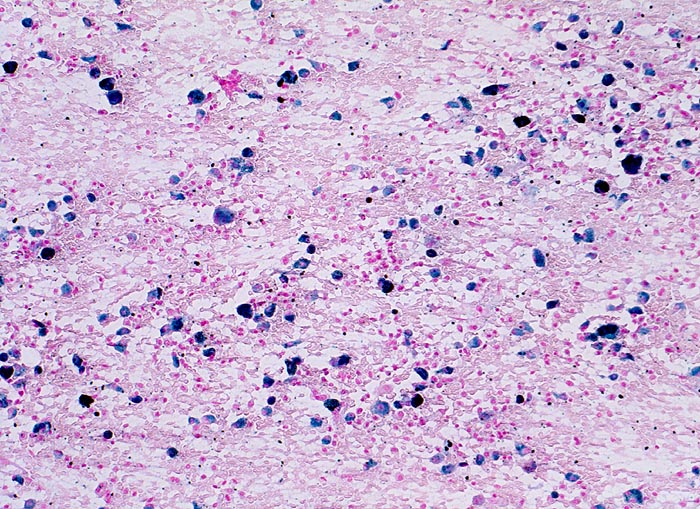

chronische Lungenstauung: Herzfehlerzellen

Im Sputumausstrich sind in der Eisenfärbung zahlreiche Makrophagen erkennbar, die eisenhaltiges Hämosiderin enthalten.

Patient mit koronarer Herzkrankheit und Linksherzinsuffizienz.